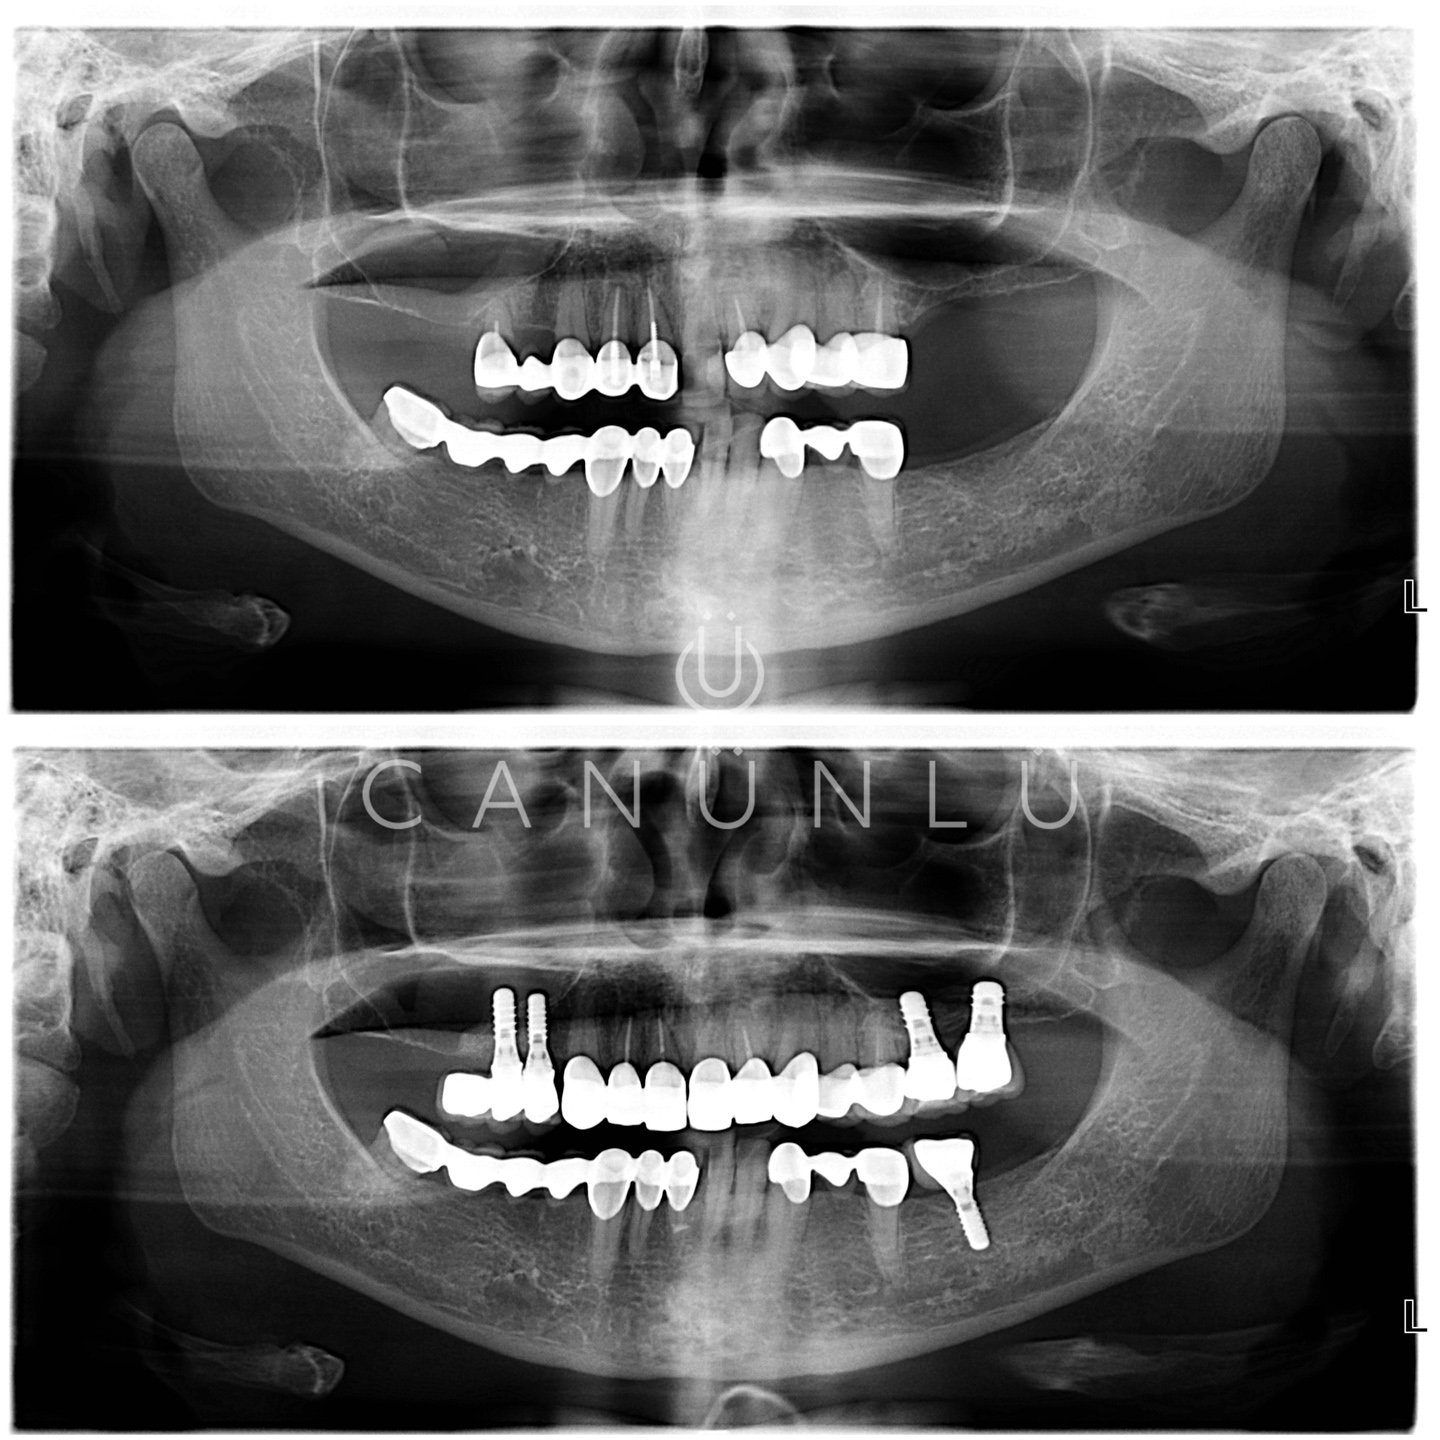

Diş İmplantları, eksik olan dişlerin yerine, çene kemiğine yerleştirilen titanyumdan yapılmış vidalardır. İmplantlar, küçük bir cerrahi işlemle çene kemiğine yerleştirilir. Bu işlemden sonra üç ay gibi kısa bir sürede tamamen çene kemiğine tutunur. Bu tutunma sonrası implant gerçek bir diş kökünün yerini alarak üzerine yapılacak protezi taşımaya hazır hale gelir.

İmplantlar; çene kemiğinde tek diş eksikliğinde, birden fazla diş eksikliğinde ve ağızda hiç diş olmadığı durumlarda uygulanmaktadır.